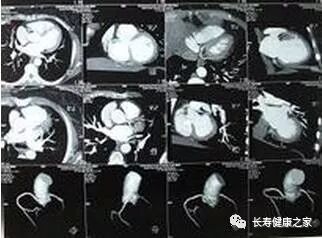

CT

像把面包切片看

CT的检查原理是X光会分层穿过人体,之后通过电脑计算后二次成像,就像把一片面包切成片来看。

优点是可以分层看,经计算后可以显示出更多的组织信息。

心 脏

排除冠心病用CT

看心功能用超声

常规的心脏结构与功能检查,心脏彩超所提供的信息已经较为充分,又简单易行。

用CT可检查冠状动脉,但冠脉CT检查辐射量较大,不适合作为常规体检。核磁虽无电磁辐射,但对冠状动脉的观察不及CT。心脏核磁则是评价心脏结构和功能的“金标准”。